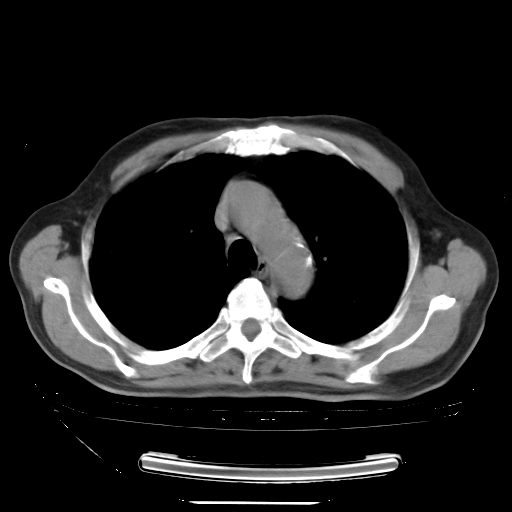

今天复查肺部CT,发现双肺广泛磨玻璃样改变。所以我把3月19日和5月9日相隔50天的肺部CT上传。请大家会诊。

2009年3月19日肺部CT片。

2009年3月19日肺部CT

大致读了系列胸部CT:纵隔窗无明显异常,肺窗:从4、27至今:主要是双肺中下野外带可见毛玻璃样改变,目前处于急性肺泡炎阶段,至于原因考虑1、结替组织或胶原血管性疾病所致?2、恶性疾病如恶组在肺部所致的表现或细支气管肺泡癌?3、药物或其它原因如肺蛋白沉着症所致肺泡炎目前不太可能?总之,明天就去请我院的呼吸科、感染科、血液科和临免专家会诊哈。